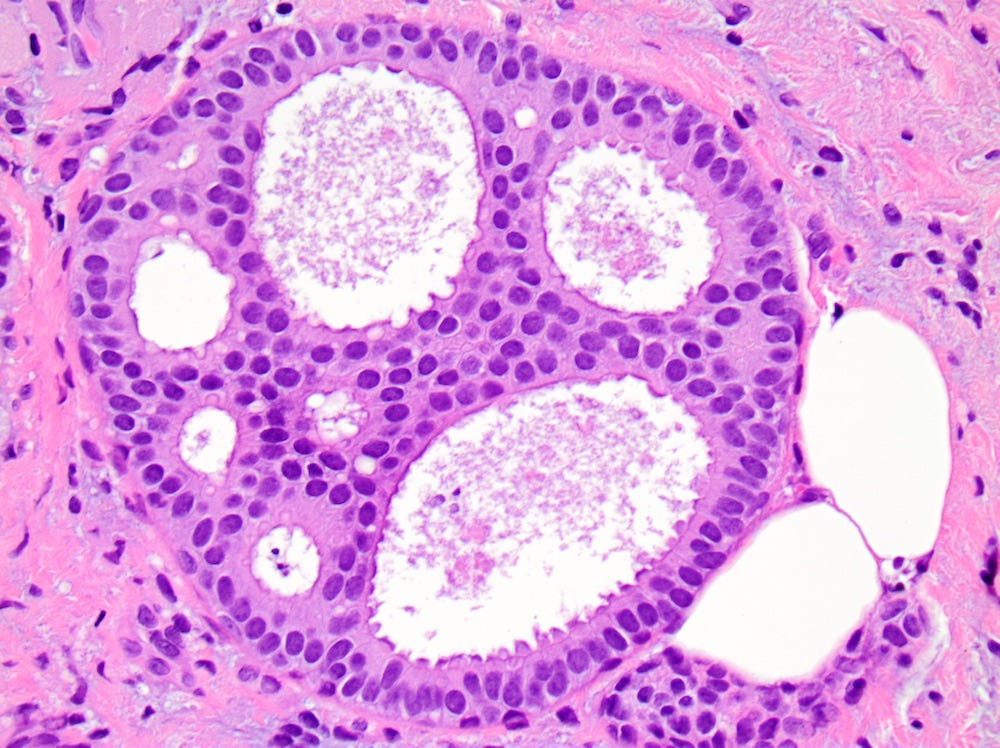

Florid lobular carcinoma in situ - microscopic images

Precursor of classic lobular carcinoma - florid lobular carcinoma in situ

Florid LCIS is a rare (< 5% of LCIS) nonclassical or variant form of lobular carcinoma in situ in which acini and ducts are markedly distended with little to no intervening stroma. It may have a mass-like architecture and includes cells with cytologic features of classic LCIS (type A or type B cells) with or without comedonecrosis and calcifications. Most cases are associated with classic LCIS or atypical lobular hyperplasia (ALH).

Florid LCIS has features of a high risk precursor lesion of invasive carcinoma including a higher upgrade rate, increased association with invasive carcinoma and more genetic complexity compared to classic LCIS.

In contrast to classic LCIS, complete surgical excision of florid LCIS is recommended.